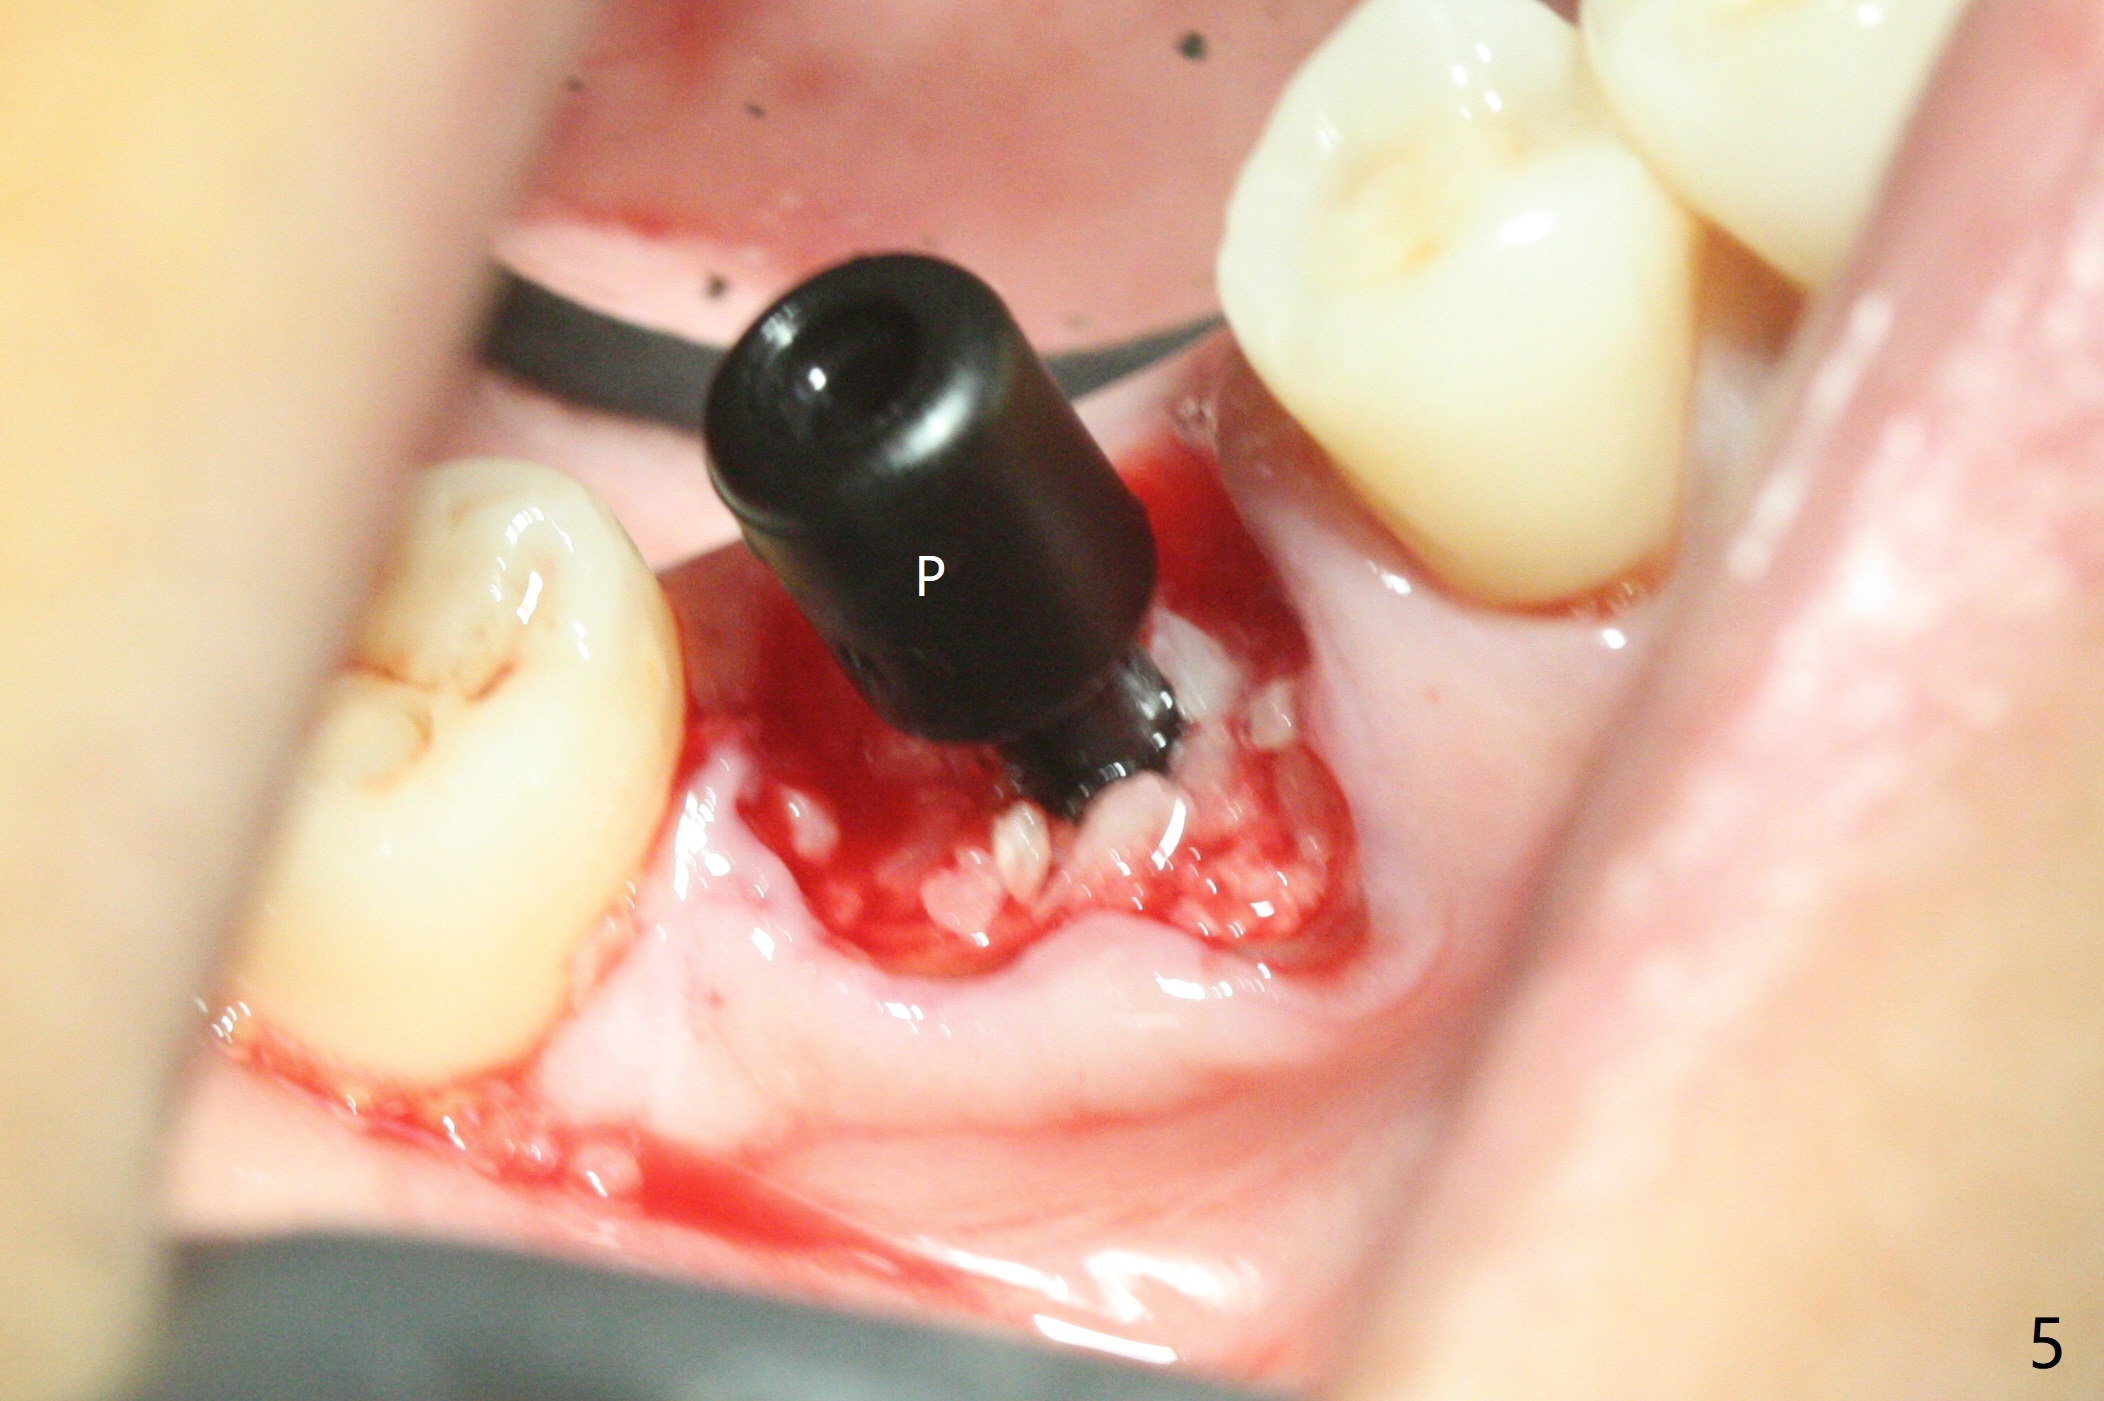

To prevent further postop buccal gingival recession at #30, socket shield is formed with removal of the residual roots (Fig.1,2 *). Osteotomy is initiated in the septum (Fig.2 S, to be flattened with bone trimmer and surgical round bur) and gradually slides slightly into the mesial socket in spite of using surgical guide (Fig.3 *: sleeve). Following 4.5x11.5 mm drill, a 4.5x8 mm Bicon implant is pressed fit; its stability is lightly enhanced with placement of sticky bone in the remaining sockets (Fig.4 *) and around the black plug (Fig.5 P). After removing the coronal portion of the plug to reduce occlusal interference, two pieces of PRF are wrapped around the remaining plug (Fig.6). The main stability of the implant is obtained when setting acrylic (A in Fig.7) is applied into the edentulous space (undercut). After acrylic setting, flowable composite (*) is added distal for further retention. One month postop, the flowable composite is detached. The provisional is sectioned; the black plug is cut. The socket heals with exposure of the mesial socket shield (Fig.8 >). The black healing plug and the mesial socket shield remains exposed 3 months postop (Fig.9). When a 4.5x6.5 mm temporary abutment is placed, the buccal gingiva is blanched and the mesial socket shield is pushed buccal (Fig.10). The implant appears to remain covered by the bone 3 months postop (Fig.11). Cortical bone starts to form crestal 7 months postop (Fig.12 arrowheads, coronavirus). The cortex seems to thicken 8 months postop (Fig.13 *).